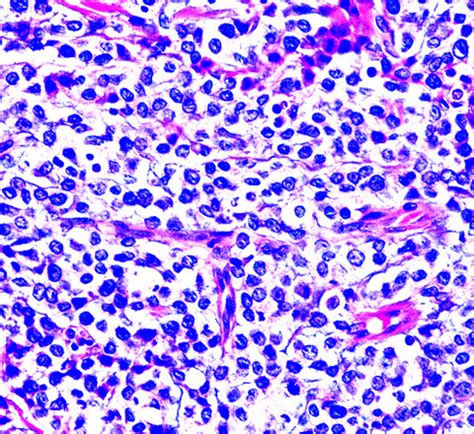

Pathology Outlines - Leukemia cutis

Pathology Outlines - Leukemia cutis from www.pathologyoutlines.com

Lc has a wide range of cutaneous manifestations, which can make it difficult to clinically distinguish. Leukemia cutis preceding systemic relapse of acute myeloid leukemia. Leukemia cutis (lc) is a nonspecific term used for cutaneous manifestations of any type of leukemia. The leukemia cells then prevent other cells in your body from behaving and functioning normally, which can have serious consequences. Related online courses on physioplus. Leukemia cutis is the infiltration of neoplastic leukocytes or their precursors into the epidermis, the dermis, or the subcutis, resulting in clinically identifiable cutaneous lesions. Learn more about the symptoms, causes, diagnosis, and treatment of leukemia. National comprehensive cancer network (nccn) guidelines. Leukaemia cutis refers to the infiltration of the skin with leukaemia cells. Get detailed information about the treatment of new and. Leukaemia cutis is an uncommon condition due to infiltration of. Leukemia cutis is the infiltration of neoplastic leukocytes or their precursors into the epidermis, the dermis, or the subcutis, resulting in clinically identifiable cutaneous lesions. Leukemia is cancer of the blood cells.

Immunophenotypic identification of acute myeloid leukemia with monocytic differentiation. Leukemia cutis is the infiltration of neoplastic leukocytes or their precursors into the epidermis, the dermis, or the subcutis, resulting in clinically identifiable cutaneous lesions. Lc and aml leukemia cutis most commonly is observed in aml compared to the other types of leukemia. Leukemia cutis is the infiltration of neoplastic leukocytes or their precursors into the epidermis, the dermis, or the subcutis, resulting in clinically identifiable cutaneous lesions. Leukemia is a cancer of the blood and bone marrow.

A doctor's guide to acute myeloid leukaemia. The differential diagnosis includes leukemia cutis, cutaneous tumor metastases, erythema multiforme, vasculitis, drug hypersensitivity reaction, sepsis (bacterial and fungal), sweet syndrome. Frater introduction acute leukemia may present in a variety of extramedullary tissues with or without. Subscriber sign in feedback select language share. Leukaemia cutis is an uncommon condition due to infiltration of. While the extramedullary collection of leukemic cells is generally regarded as myeloid sarcoma. National comprehensive cancer network (nccn) guidelines. Leukemia usually involves the white blood cells. Your white blood cells are potent infection fighters — they normally grow and divide in an orderly way, as your body needs them. Leukemia is cancer of the blood cells. Leukemia is a type of blood cancer that affects your bone marrow, which makes blood. It is common in children, but leukemia most often occurs in adults older than 55. Leukemia cutis characteristically demonstrates the infiltration of the skin by neoplastic leukocytes.